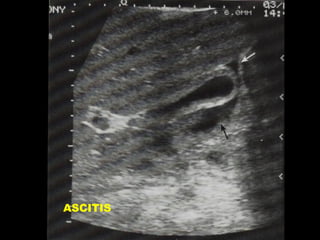

FLUIDO PERICOLECISTICO

• ASCITIS GENERALIZADA

• PERFORACION VESICULAR

• INFLAMACION O PERFORACION

DE ORGANOS VECINOS

.

ASCITIS